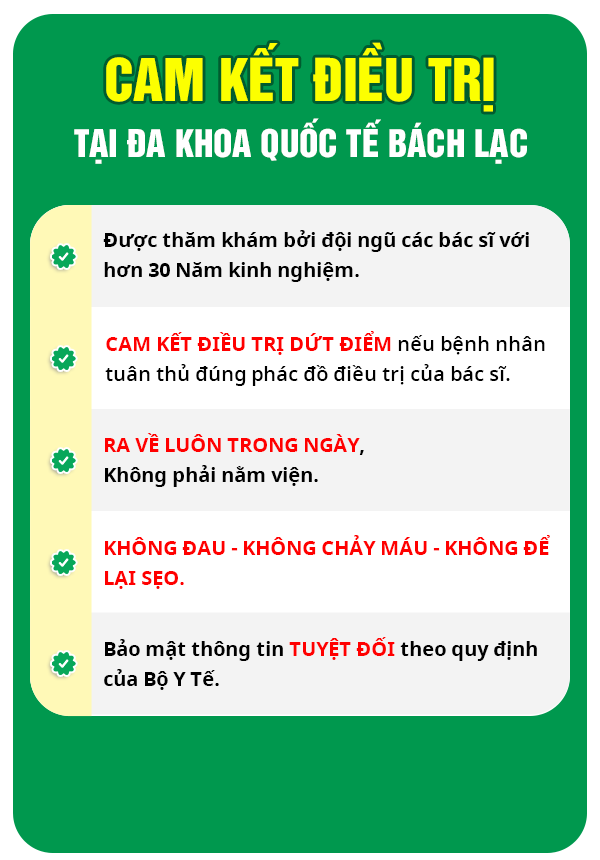

Hiện nay phòng khám Đa khoa Quốc tế Bách Lạc là một trong những địa chỉ uy tín khám chữa bệnh nam – phụ khoa, các bệnh đường tiết niệu, hậu môn – trực tràng hiệu quả.

Phòng khám được đánh giá cao bởi:

![]() Phòng khám có giấy phép hoạt động do Sở Y tế cấp.

Phòng khám có giấy phép hoạt động do Sở Y tế cấp.

![]() Đội ngũ bác sĩ có trình độ chuyên môn cao, nhiều năm kinh nghiệm.

Đội ngũ bác sĩ có trình độ chuyên môn cao, nhiều năm kinh nghiệm.

![]() Tất cả công nghệ, máy móc, vật liệu phẫu thuật đều nhập từ nước ngoài.

Tất cả công nghệ, máy móc, vật liệu phẫu thuật đều nhập từ nước ngoài.

![]() Phòng khám được đầu tư với nhiều cơ sở vật chất tiện nghi, phòng thủ thuật sạch sẽ, vô trùng thường xuyên.

Phòng khám được đầu tư với nhiều cơ sở vật chất tiện nghi, phòng thủ thuật sạch sẽ, vô trùng thường xuyên.

![]() Dịch vụ y tế chuyên nghiệp với thủ tục nhanh gọn, phục vụ chu đáo, bảo mật thông tin.

Dịch vụ y tế chuyên nghiệp với thủ tục nhanh gọn, phục vụ chu đáo, bảo mật thông tin.

![]() Chi phí thăm khám được niêm yết công khai theo đúng quy định của Sở Y tế.

Chi phí thăm khám được niêm yết công khai theo đúng quy định của Sở Y tế.

![]() Thời gian mở cửa từ 7h30 đến 20h các ngày trong tuần, kể cả các ngày lễ tết.

Thời gian mở cửa từ 7h30 đến 20h các ngày trong tuần, kể cả các ngày lễ tết.